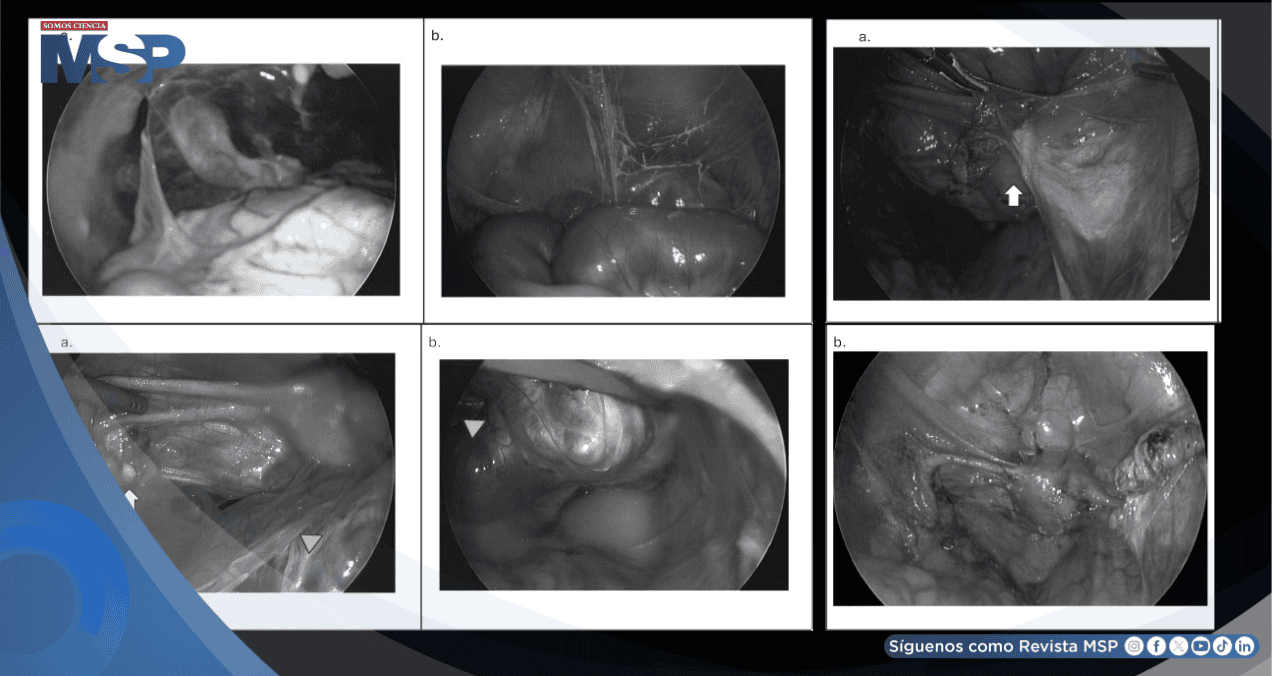

Durante la cirugía, los médicos encontraron un escenario devastador en su pelvis. Los órganos estaban cubiertos por un entramado de cicatrices y adherencias que los pegaban entre sí y a las paredes abdominales.

Sus trompas de Falopio, esenciales para la concepción, estaban enrojecidas, bloqueadas y con su estructura dañada. El útero presentaba cicatrices internas, y lo más crítico fue el estado de sus ovarios.

El ovario izquierdo estaba tan adherido que era difícil de ver, y el derecho, envuelto en un gran quiste y tejido cicatricial, no pudo ser localizado a pesar de los esfuerzos por restaurar la anatomía normal. En esencia, el tejido ovárico sano parecía haber sido destruido.